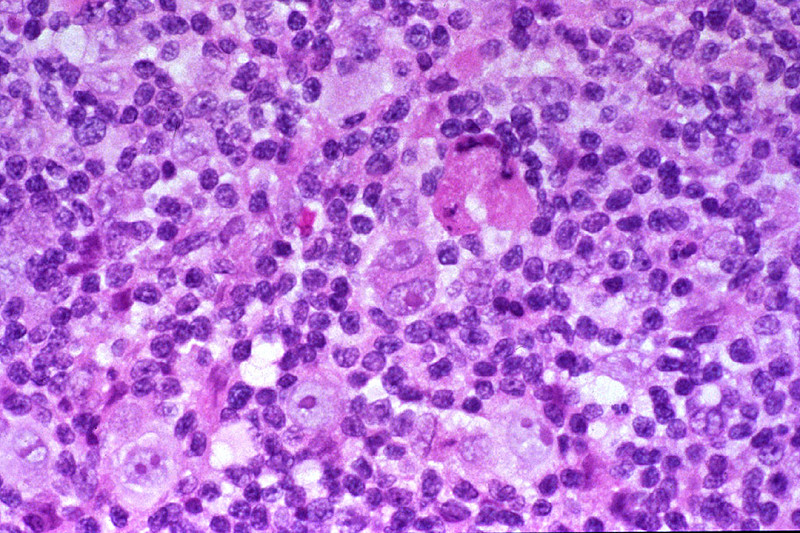

Микропрепараты: Лимфогранулематоз и Нодулярный Склероз

Раздел: Секреты мастерства